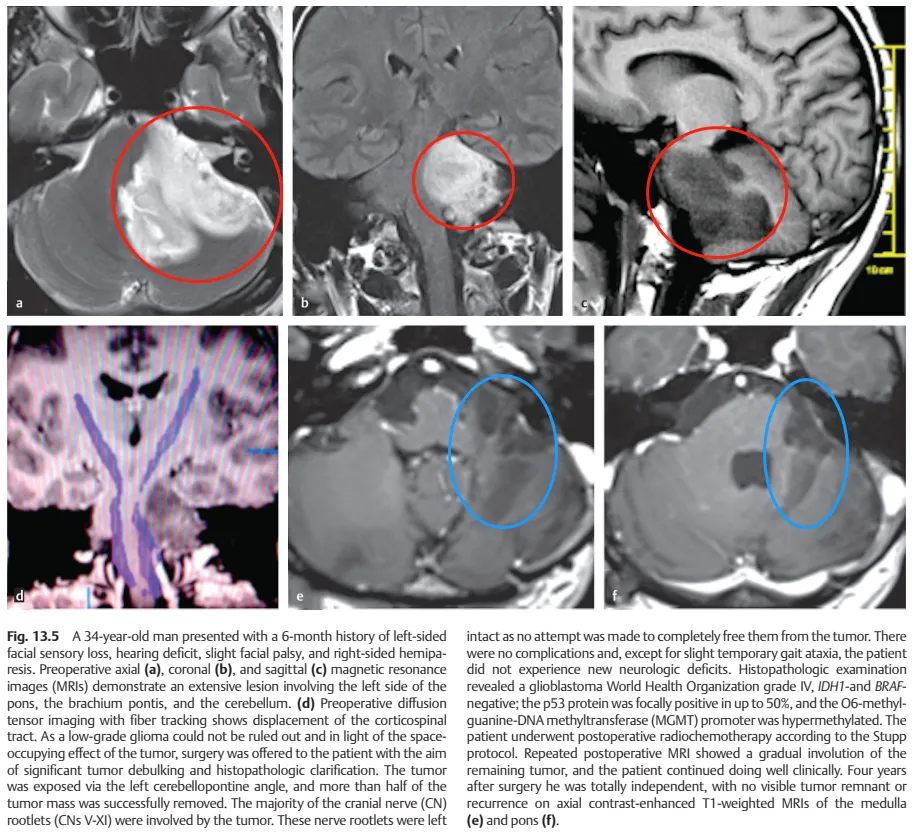

经磁共振成像(MRI)检查发现脑干区域存在巨大肿瘤,累及左侧桥脑、脑桥臂及小脑,肿瘤压迫邻近面神经与听神经导致上述症状。图a、b、c显示脑干巨大占位病变,图d术前扩散张量成像可见肿瘤压迫致皮质脊髓束移位。

鉴于不能排除低级别胶质瘤可能,且存在明显占位效应,医疗团队建议尽早手术明确病理诊断。但由于脑干手术复杂度高,瘫痪风险显著。治疗团队INC德国巴特朗菲教授采用乙状窦后入路,经左侧桥小脑角暴露肿瘤,成功切除50%以上瘤体。因肿瘤累及多数颅神经(CNs V-XI),为避免严重神经功能损伤未行全切。术后除短暂性步态共济失调外,未出现新发神经功能障碍。

术后病理确诊为胶质母细胞瘤,IDH1与BRAF呈阴性,p53蛋白局部阳性率达50%,O6-甲基鸟嘌呤DNA甲基转移酶(MGMT)启动子高度甲基化。患者按Stupp方案完成放化疗,随访MRI显示残余肿瘤逐渐消退。术后4年随访显示患者可完全独立生活,延髓(图e)与脑桥(图f)轴位T1加权增强MRI未见肿瘤复发征象。